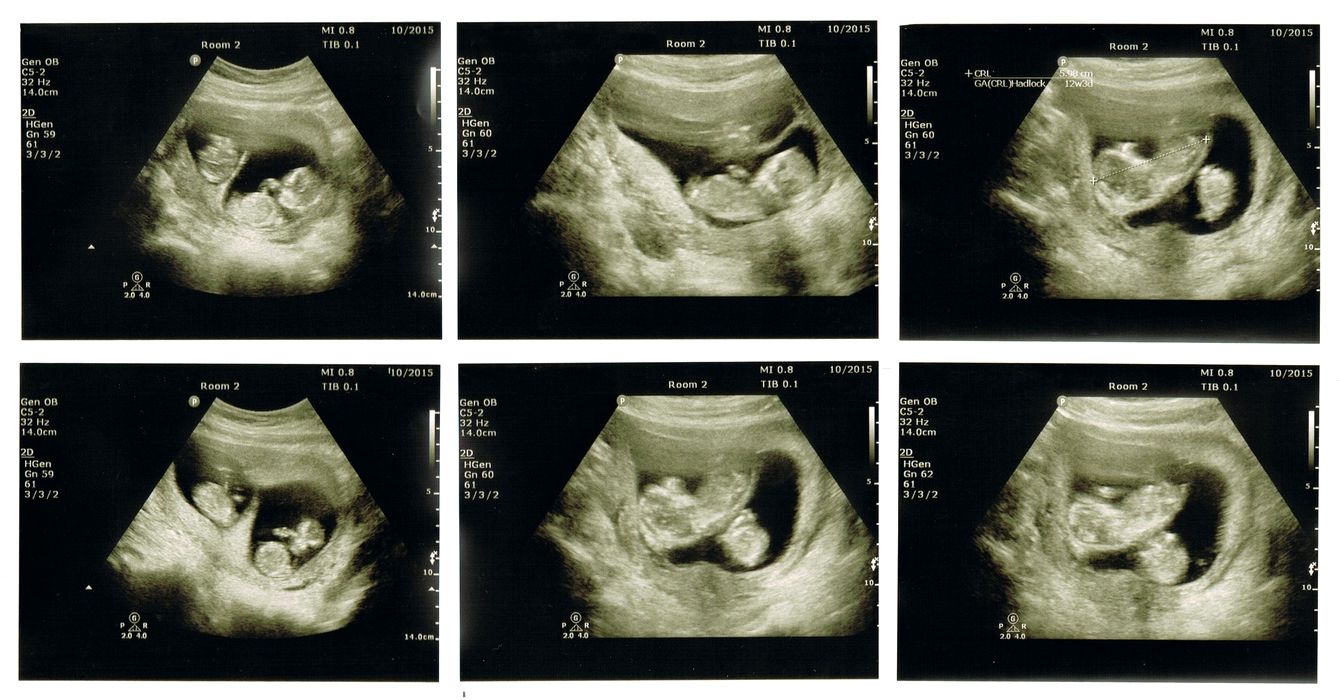

Chirurgii au efectuat cu succes prima operație pe creier la un făt aflat încă în uter, reparând o malformație vasculară potențial mortală din adâncul creierului în curs de dezvoltare. Folosind ultrasunete pentru a-i ghida pe […]